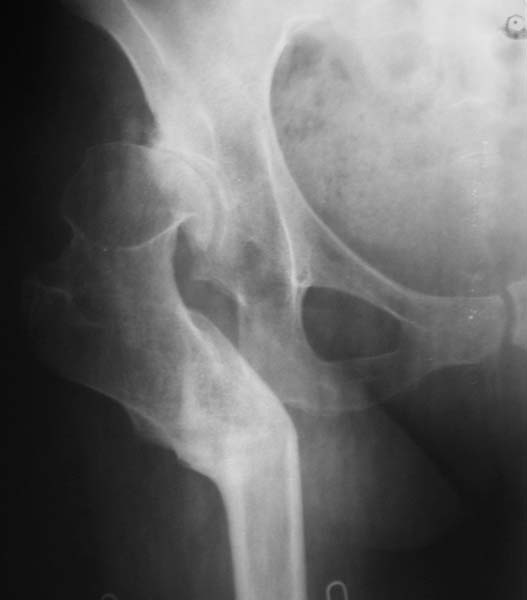

Уважаемые коллеги!Женщина, 35 летВ прошлом по поводу врожденного вывиха бедра перенесла операцию остеотомии по Шанцу

с удлинением правой ноги за счет бедра на уровне диафиза. В последнее время прогрессируют боли в правом тазобедренном суставе, порочное положение правой ноги, затруднена ходьба.Вопросы:1) Целесообразно ли эндопротезирование правого тазобедренного сустава?2) Целесообразный ли следующие действия: канал бедренной кости предполагаем вскрыть для введения ножки протеза на высоте угловой деформации, предполагаем низведение большого вертела с мышцами; протез будет подобран индивидуально, предполагается умеренная версия?В приложении рентгенограммы и трехмерная КТ.В цветном и более качественном варианте КТ размещена здесь